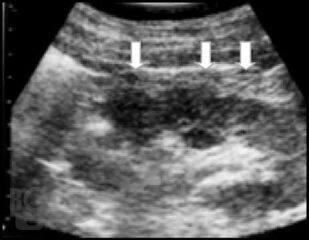

Настоящая монография предназначена для врачей – лучевых диагностов, урологов, хирургов, терапевтов, семейных врачей, а также студентов медицинских вузов, и посвящена применению лучевых методов исследования в диагностике различных форм острого гнойного пиелонефрита.

В монографии детально показана разнообразная лучевая семиотика при апостематозном пиелонефрите, карбункуле и абсцессе почки, а также представлены различные современные методы лечения с динамикой воспалительных изменений в паренхиме почки.